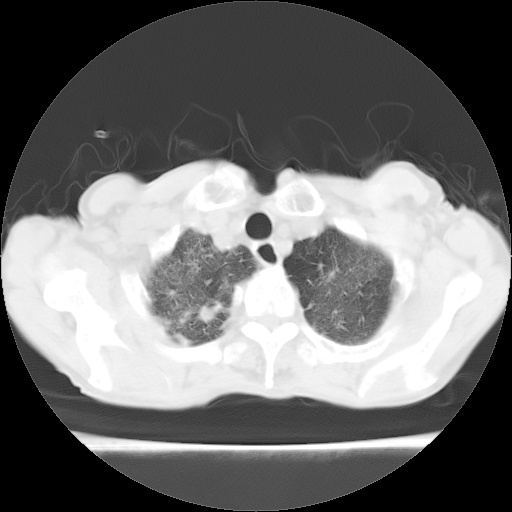

病人发热、气促就诊。原二周前已行ct扫描,当时诊断为双肺下叶、右肺中叶支气管扩张并感染,双肺上叶片状渗出性病变。今天复查胸部ct,双肺下叶支气管扩张并感染病灶较前明显吸收,但双肺上叶渗出性病变较范围较前明显增大。

双肺多发大片状、斑片状高密度渗出影,部分实变,考虑病毒性肺炎。